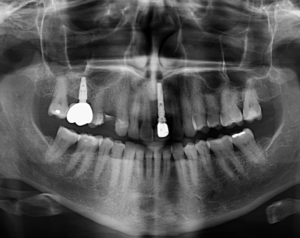

Paciente femenino de 48 años de edad, es referido al Instituto de Diagnóstico Maxilofacial – IDM para evaluación general.

En la radiografía panorámica (Figura 1), se aprecia pieza 13 en posición ectópica y además se observa imagen radiolúcida proyectados en tercio apical de pieza 33.

Radiografia Panorámica